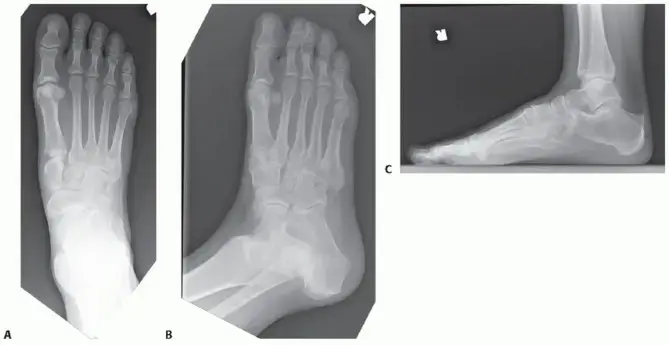

صورة توضيحية لـ دمج منتصف القدم (تثبيت مفصل منتصف القدم): دليل شامل للمرضى بقلم الأستاذ الدكتور محمد هطيف

يقوم الأستاذ الدكتور محمد هطيف بتقييم شامل للمريض، بما في ذلك الفحص السريري الدقيق والتصوير بالأشعة السينية أو الرنين المغناطيسي، لتحديد مدى تضرر المفاصل وتأثيرها على وظيفة القدم، مما يمكنه من وضع خطة علاجية مخصصة لكل حالة.

• المتابعة مع الأستاذ الدكتور محمد هطيف: سيقوم بتقييم تقدم الشفاء من خلال فحص القدم والأشعة السينية للتأكد من أن العظام بدأت في الالتحام.

• التغيير إلى حذاء/جزمة المشي القابلة للإزالة (Walking Boot): إذا كانت الأشعة السينية تظهر التئامًا كافيًا، فقد يُسمح لك بالتبديل من الجبيرة إلى حذاء مشي خاص يمكن إزالته، والذي يوفر الدعم والحماية.